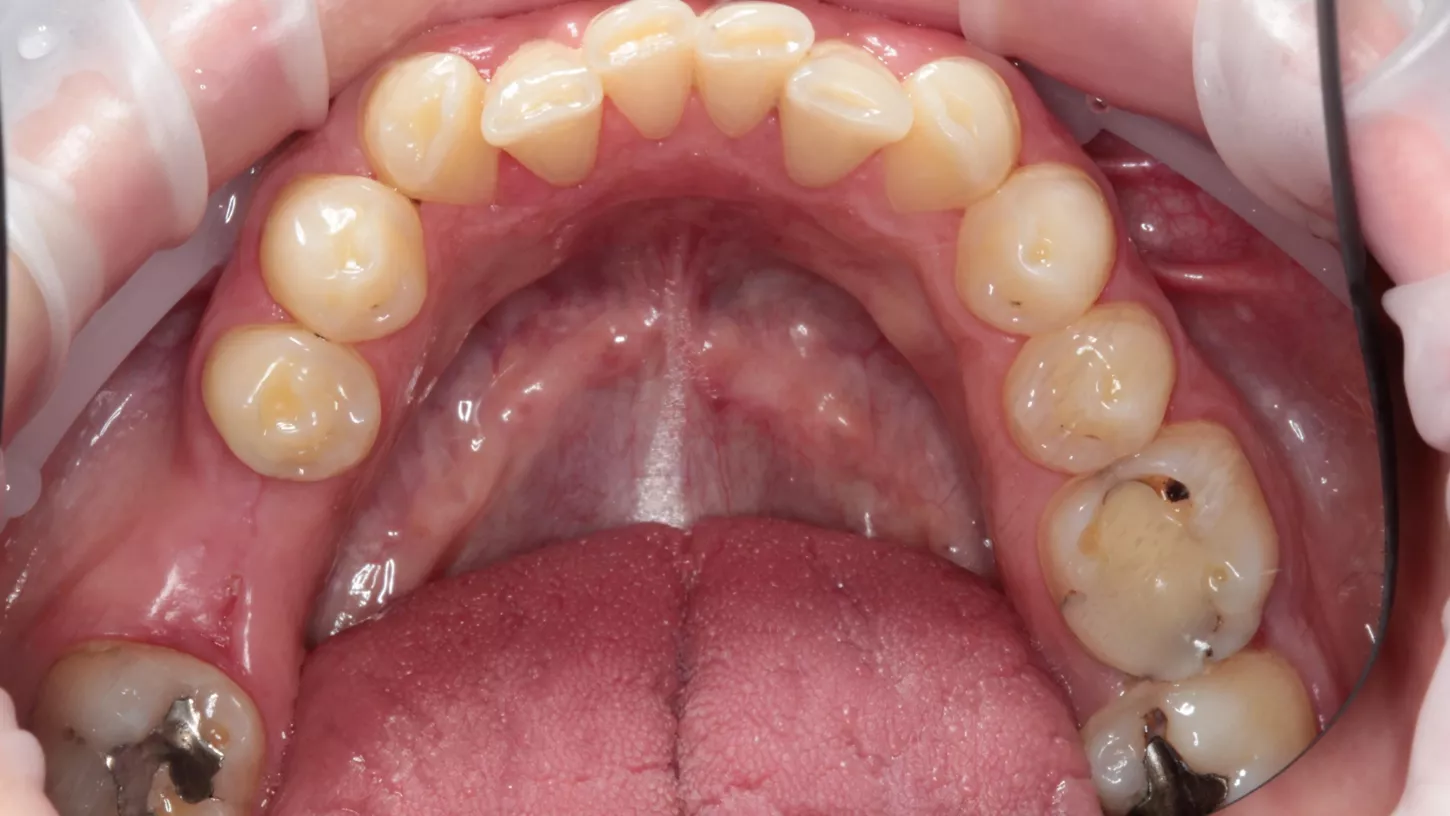

Cet homme charmant et en bonne santé, âgé d'une quarantaine d'années, a consulté pour remplacer la LR6 manquante, qui avait été extraite il y a trois mois en raison d'un abcès. Son objectif principal était de restaurer la fonction, et ses attentes esthétiques étaient faibles. En intra-oral, il a présenté la LR6 manquante, un espace vertical et horizontal suffisant pour remplacer la dent manquante, mais des signes clairs de la parafonction actuelle. L'hygiène bucco-dentaire était satisfaisante. Le patient était fumeur (5 à 10 par jour). Toutes les options pour remplacer la dent manquante ont été discutées : accepter l'espace, une prothèse, un bridge ou un implant dentaire. Tous les risques et avantages de chaque option ont été présentés, mais le patient n'était intéressé que par l'implant.

Situation initiale

1a. 1b. Vue occlusale pré-opératoire.